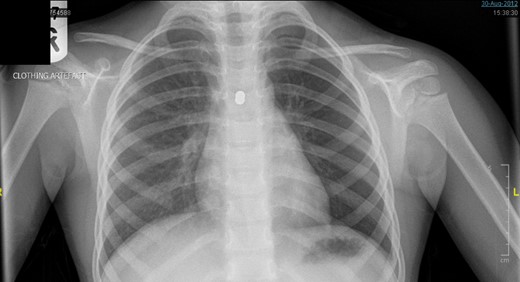

A 3-year-old girl was referred to the asthma clinic with a 3-month history of morning cough and wheeze. She was seen multiple times by her general practitioner (GP) who initially diagnosed her with upper respiratory tract infection. Her symptoms persisted despite salbutamol inhaler treatment so the GP organised a chest x-ray (CXR) (Fig. 1). It was reported that the left lung was translucent with reduced peripheral lung markings: finding consistent with asthma with bronchial plugging or a post infective bronchiolitis. It also showed a round radio-opaque FB over the left main bronchus. However, this was labelled as ‘Clothing Artefact’ on the actual radiograph and therefore did not alarm the GP or the reporting radiologist. A repeated PA CXR (Fig. 2) was undertaken in the asthma clinic where all clothes and hair were removed from the thorax. This confirmed the presence of a metallic FB in the left main bronchus and the patient was immediately admitted for bronchoscopy and removal of the FB.

Initial posterior–anterior chest x-ray (CXR) demonstrated a translucent left lung with reduced peripheral lung markings. There is also a dense rounded foreign body projected over the left main bronchus. A label of ‘CLOTHING ARTEFACT’ was placed in the left upper corner of this CXR.